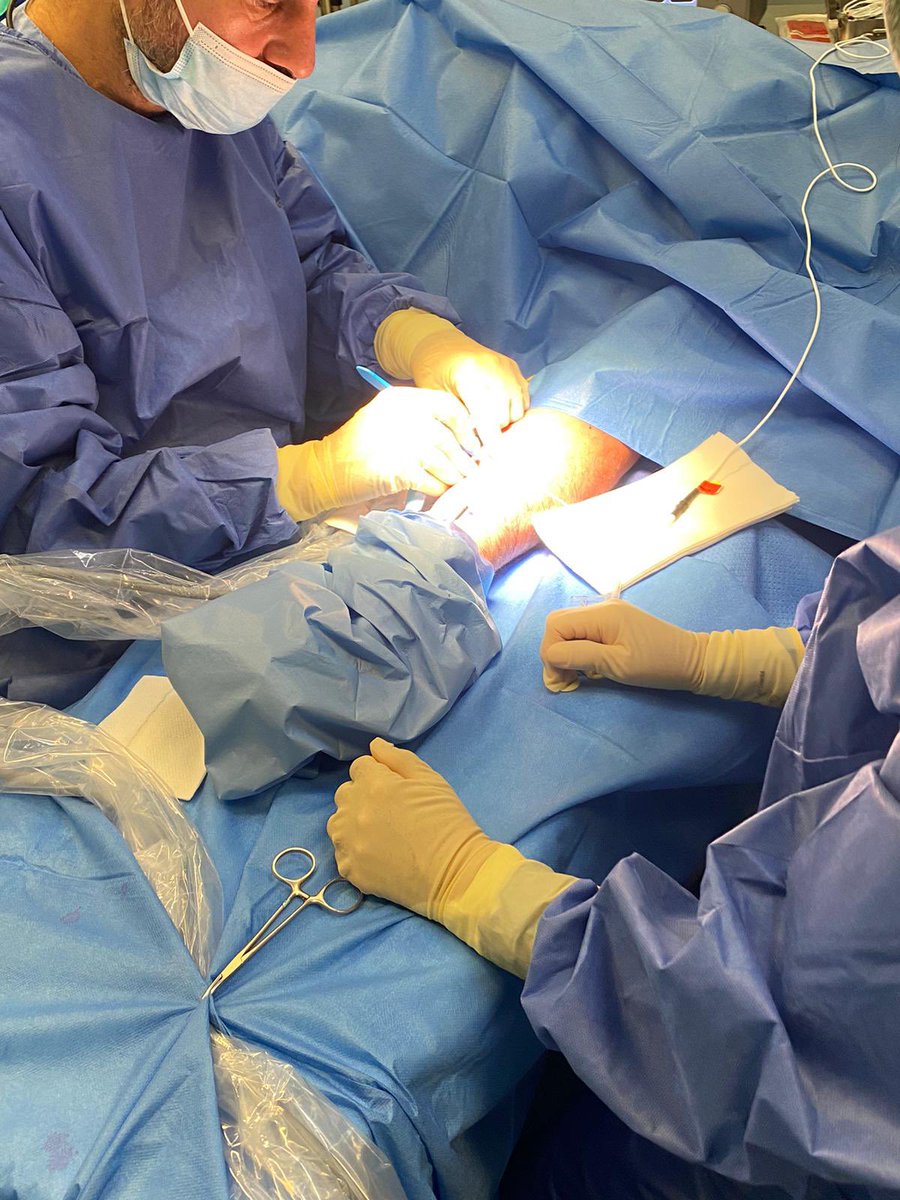

Innovando en el tratamiento del dolor pélvico crónico. Implante exitoso de electrodos de neuroestimulación Boston Scientific en nervios pudendos, bajo control ecográfico y radiológico. Mejoría del dolor en menos de 24 horas de un 90% #granequipo #siempreinnovando #dolorcrónico

[email protected] Boston Scientific Gracias Noelia 😊. La paciente italiana 61 a dolor neuropatico severo perineal , lo refería sobretodo anal y 1/3 externo vagina. Gran afectación ritmo intestinal, abuso de laxantes. 5 años de evolución y muchos especialistas previos. A. M. lo explica mejor que puso el derecho